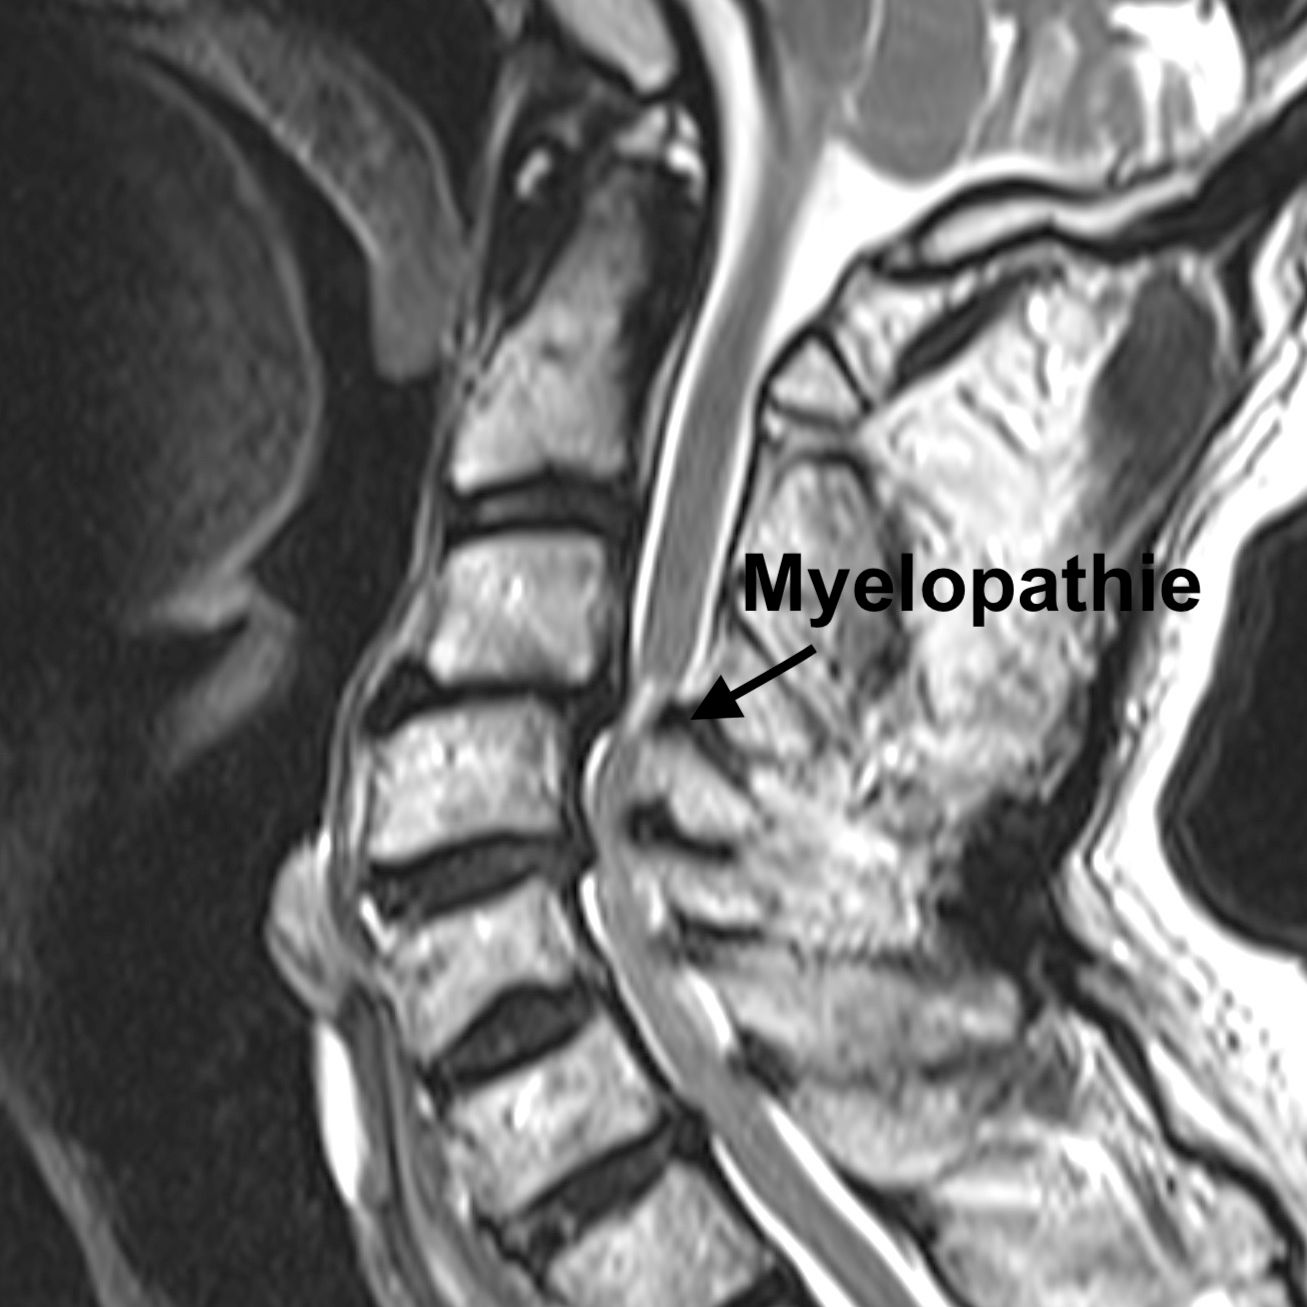

Die Spinalkanalstenose - Einengung des Wirbelkanals an der Halswirbelsäule

Bei einer Spinalkanalstenose an der Halswirbelsäule ist der Wirbelkanal – also der Raum, durch den das Rückenmark verläuft – verengt. Diese Einengung kann Druck auf das Rückenmark ausüben. Wenn dadurch die Funktion des Rückenmarks gestört ist, spricht man von einer Myelopathie. Typische Beschwerden können Kribbeln, Schwäche oder Unsicherheit in Armen und Beinen, Gangstörungen oder feinmotorische Probleme (z. B. beim Schreiben oder Knöpfen) sein. In fortgeschrittenen Fällen kann es auch zu Problemen mit der Blasen- oder Darmkontrolle kommen. In leichten Fällen kann eine Behandlung mit Physiotherapie erfolgen, in fortgeschrittenen Fällenist meistens eine Operation nötig, um den Druck vom Rückenmark zu nehmen.